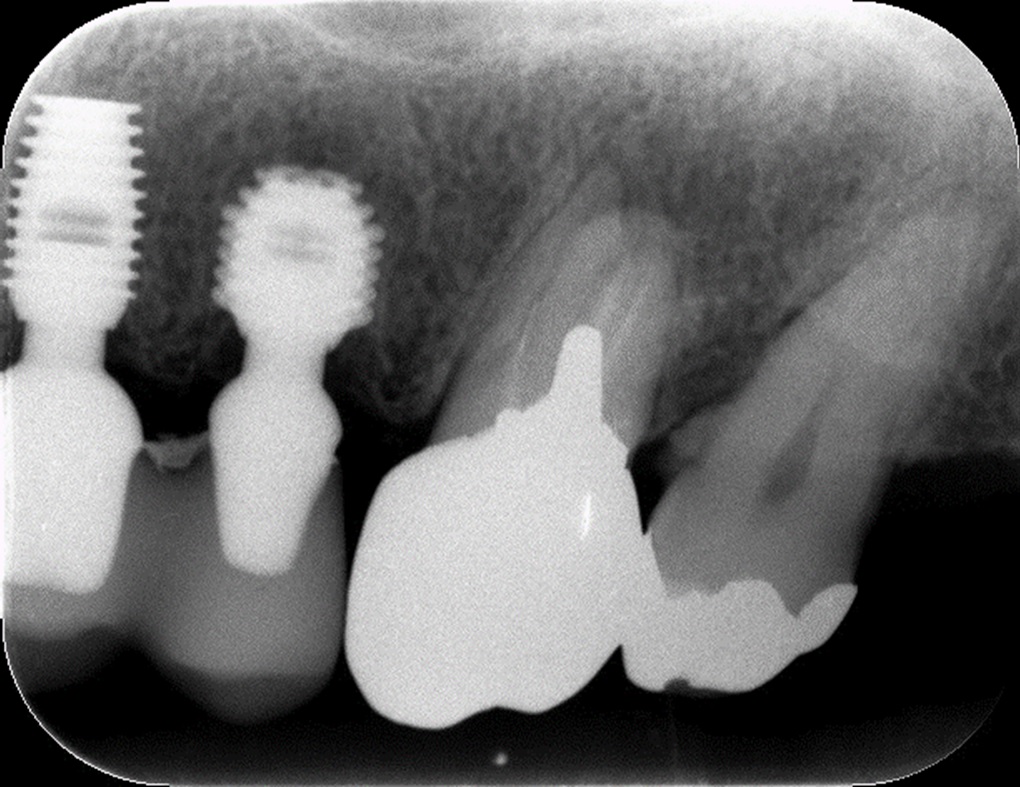

3mm以下になると、骨を作る量が多くなりますので、頬側から窓をあけて横から直接、骨補填剤を入れて骨を作ります。その際、多くのインプラントメーカーが採用するスクリュータイプのインプラントでは、インプラントが完全に固定できず、同時にインプラントを入れてしまうのは難しくなります。長いインプラントを薄い骨で固定すると不安定です。しかし、バイコンというショートインプラントを使用すると頬側に開けた窓から直接、インプラント本体を入れることができることに気づきました。

その方が患者様にとっては、手術回数が2回から1回に減る事になるので、肉体的負担も金銭的負担も減り、きわめて有効であると思います。他のメーカーのインプラントでは、長すぎて入れることができません。

バイコンインプラントが短いからこそできる方法です。

また、実際に今年の春から3症例ほどこの方法でトライしました。無理にしてしたわけではなく、できそうな場合のみ新しい方法でしてみるという同意を得てから手術しました。一応1次手術は全て成功しています。手術後は、10ヶ月くらいそのまま放置して、補填剤が固まるのを待ちますので、今は待っている状態です。